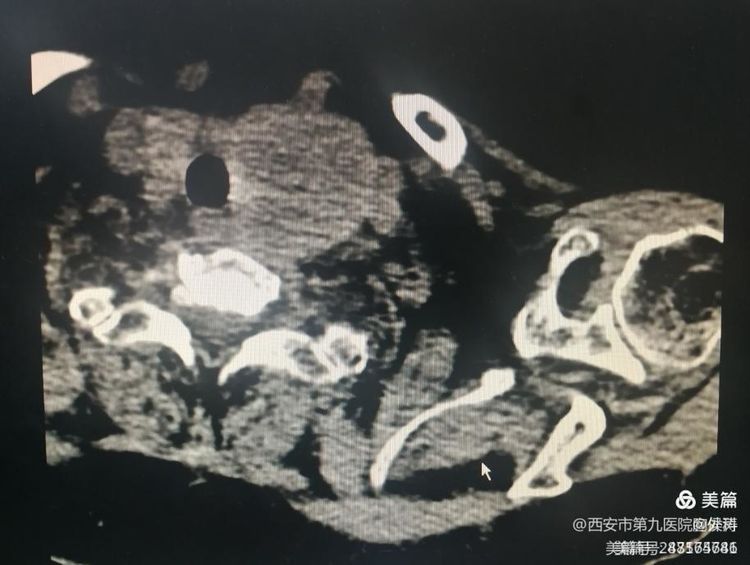

一名76岁聋哑女性患者因咳嗽、咳痰住院治疗,伴有高血压、心脏病,完善检查后发现甲状腺结节,超声见左侧甲状腺实性结节大小约30.0mm×44.7mm,TI-RADS4类,穿刺结果提示为甲状腺良性肿瘤,患者无法耐受手术治疗,科室马德茂副主任医师为患者行超声引导下甲状腺结节微波消融术。